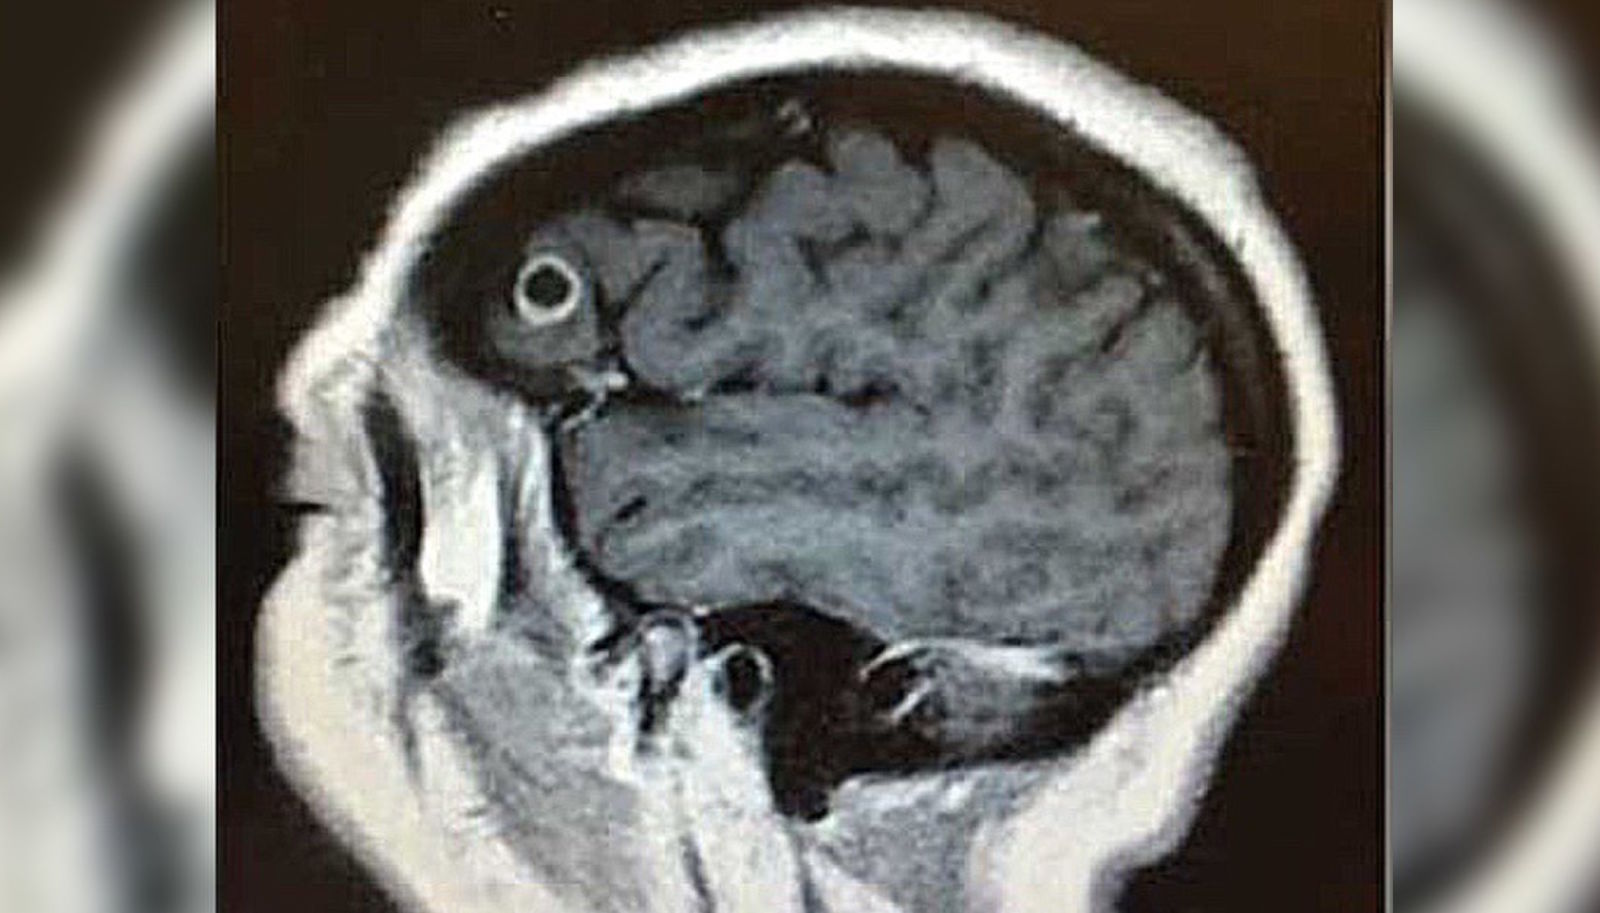

Esta mujer tuvo una enorme tenia viviendo un año en su cerebro, y fue la mejor noticia que le pudieron dar

Pocas veces en la vida te alegras de que los médicos te digan que tienes una tenia en el cuerpo desde hace un año. El caso médico de Rachel Palma es una de esas ocasiones. Cuando le dijeron que tenía un gusano encerrado en su cerebro Palma no podía estar más feliz.